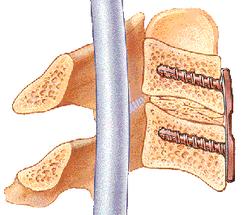

12 virginia spine institute reviews. The most common spinal disorders and conditions treated by sbi are cervical and lumbar spinal stenosis and disc herniation. 25.01.2019 · virginia spine institute has been providing elite spinal healthcare for over 25 years, improving the lives of over 85,000 patients suffering from back or neck conditions.

Today, under his leadership, virginia spine specialists strives to be on the cutting edge of minimally invasive procedures and techniques. A free inside look at company reviews and salaries posted anonymously by employees. Chairman, residency and fellowship program director. Uncover why virginia spine institute is the best company for you.